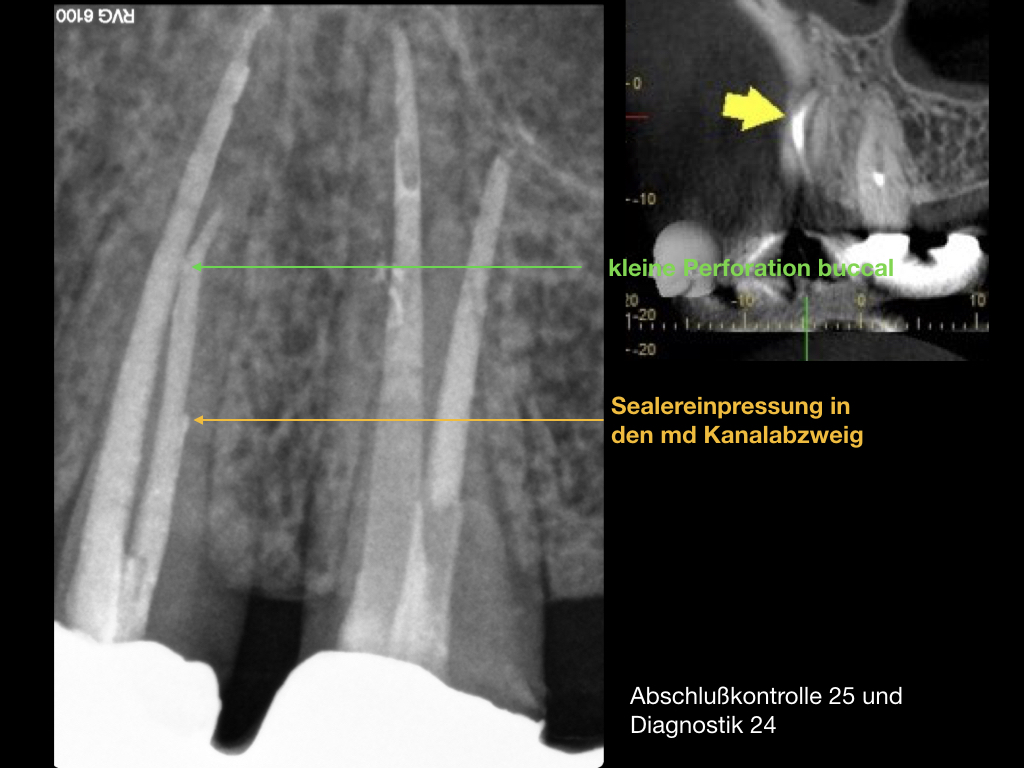

Es ist zu sehen … (2)